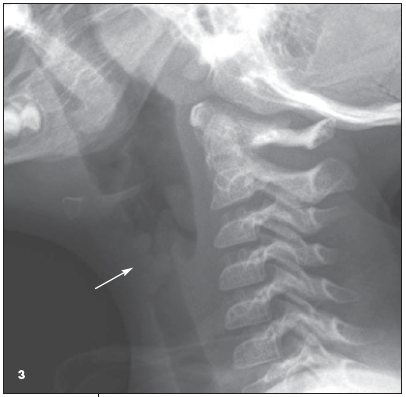

and microdebridement of papillomas on her larynx, oropharynx, hypopharynx, and esophagus. At that time, additional lesions were also identified on her uvula, tonsils, and epiglottis. Unfortunately, this child's disease was fairly severe and tenacious; at the time of writing, she has undergone 9 more debulking procedures for her recurrent papillomatosis. As time went on, the lesions progressed to involve the true and false cords fairly extensively, leaving the patient at times with a very small glottic lumen. Lesions were eventually seen below the cords as well. A follow-up airway radiograph obtained 6 months after her initial presentation (Figure 3) showed, in addition to the original lesion, a bulky soft tissue mass at the level of the vocal cords (white arrow).